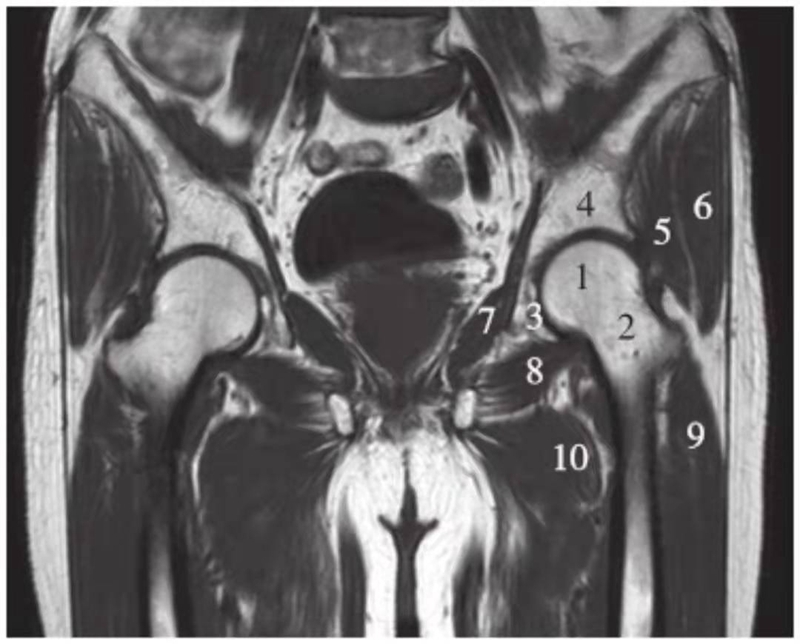

正常髋关节经股骨头中心层面T1WI像

1.股骨头;2.股骨颈;3.髋臼窝内脂肪;4.髂骨;5.臀小肌;6.臀中肌;7.闭孔内肌;8.闭孔外肌;9.股外侧肌;10.股内侧肌